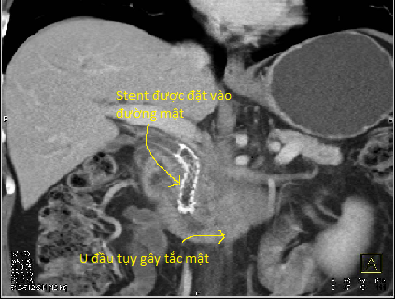

Qua thăm khám phát hiện các dấu hiệu bất thường, bác sỹ sẽ cho làm các xét nhiệm kiểm tra: xét nghiệm máu, chất chỉ điểm khối u, siêu âm, vv…Trong các xét nghiệm để chẩn đoán ung thư tụy, chụp cắt lớp vi tính có vai trò quan trọng nhất, bởi qua đó bác sỹ không những phát hiện khối u tụy mà còn đánh giá mức độ lan rộng khối u, tình trạng di căn hạch, … qua đó giúp đánh giá khả năng phẫu thuật triệt căn cũng như khả năng can thiệp để giải quyết các biến chứng do u gây ra: tắc mật (đặt stent đường mật, dẫn lưu đường mật qua da), đau (phong bế đám rối thần kinh giảm đau), …